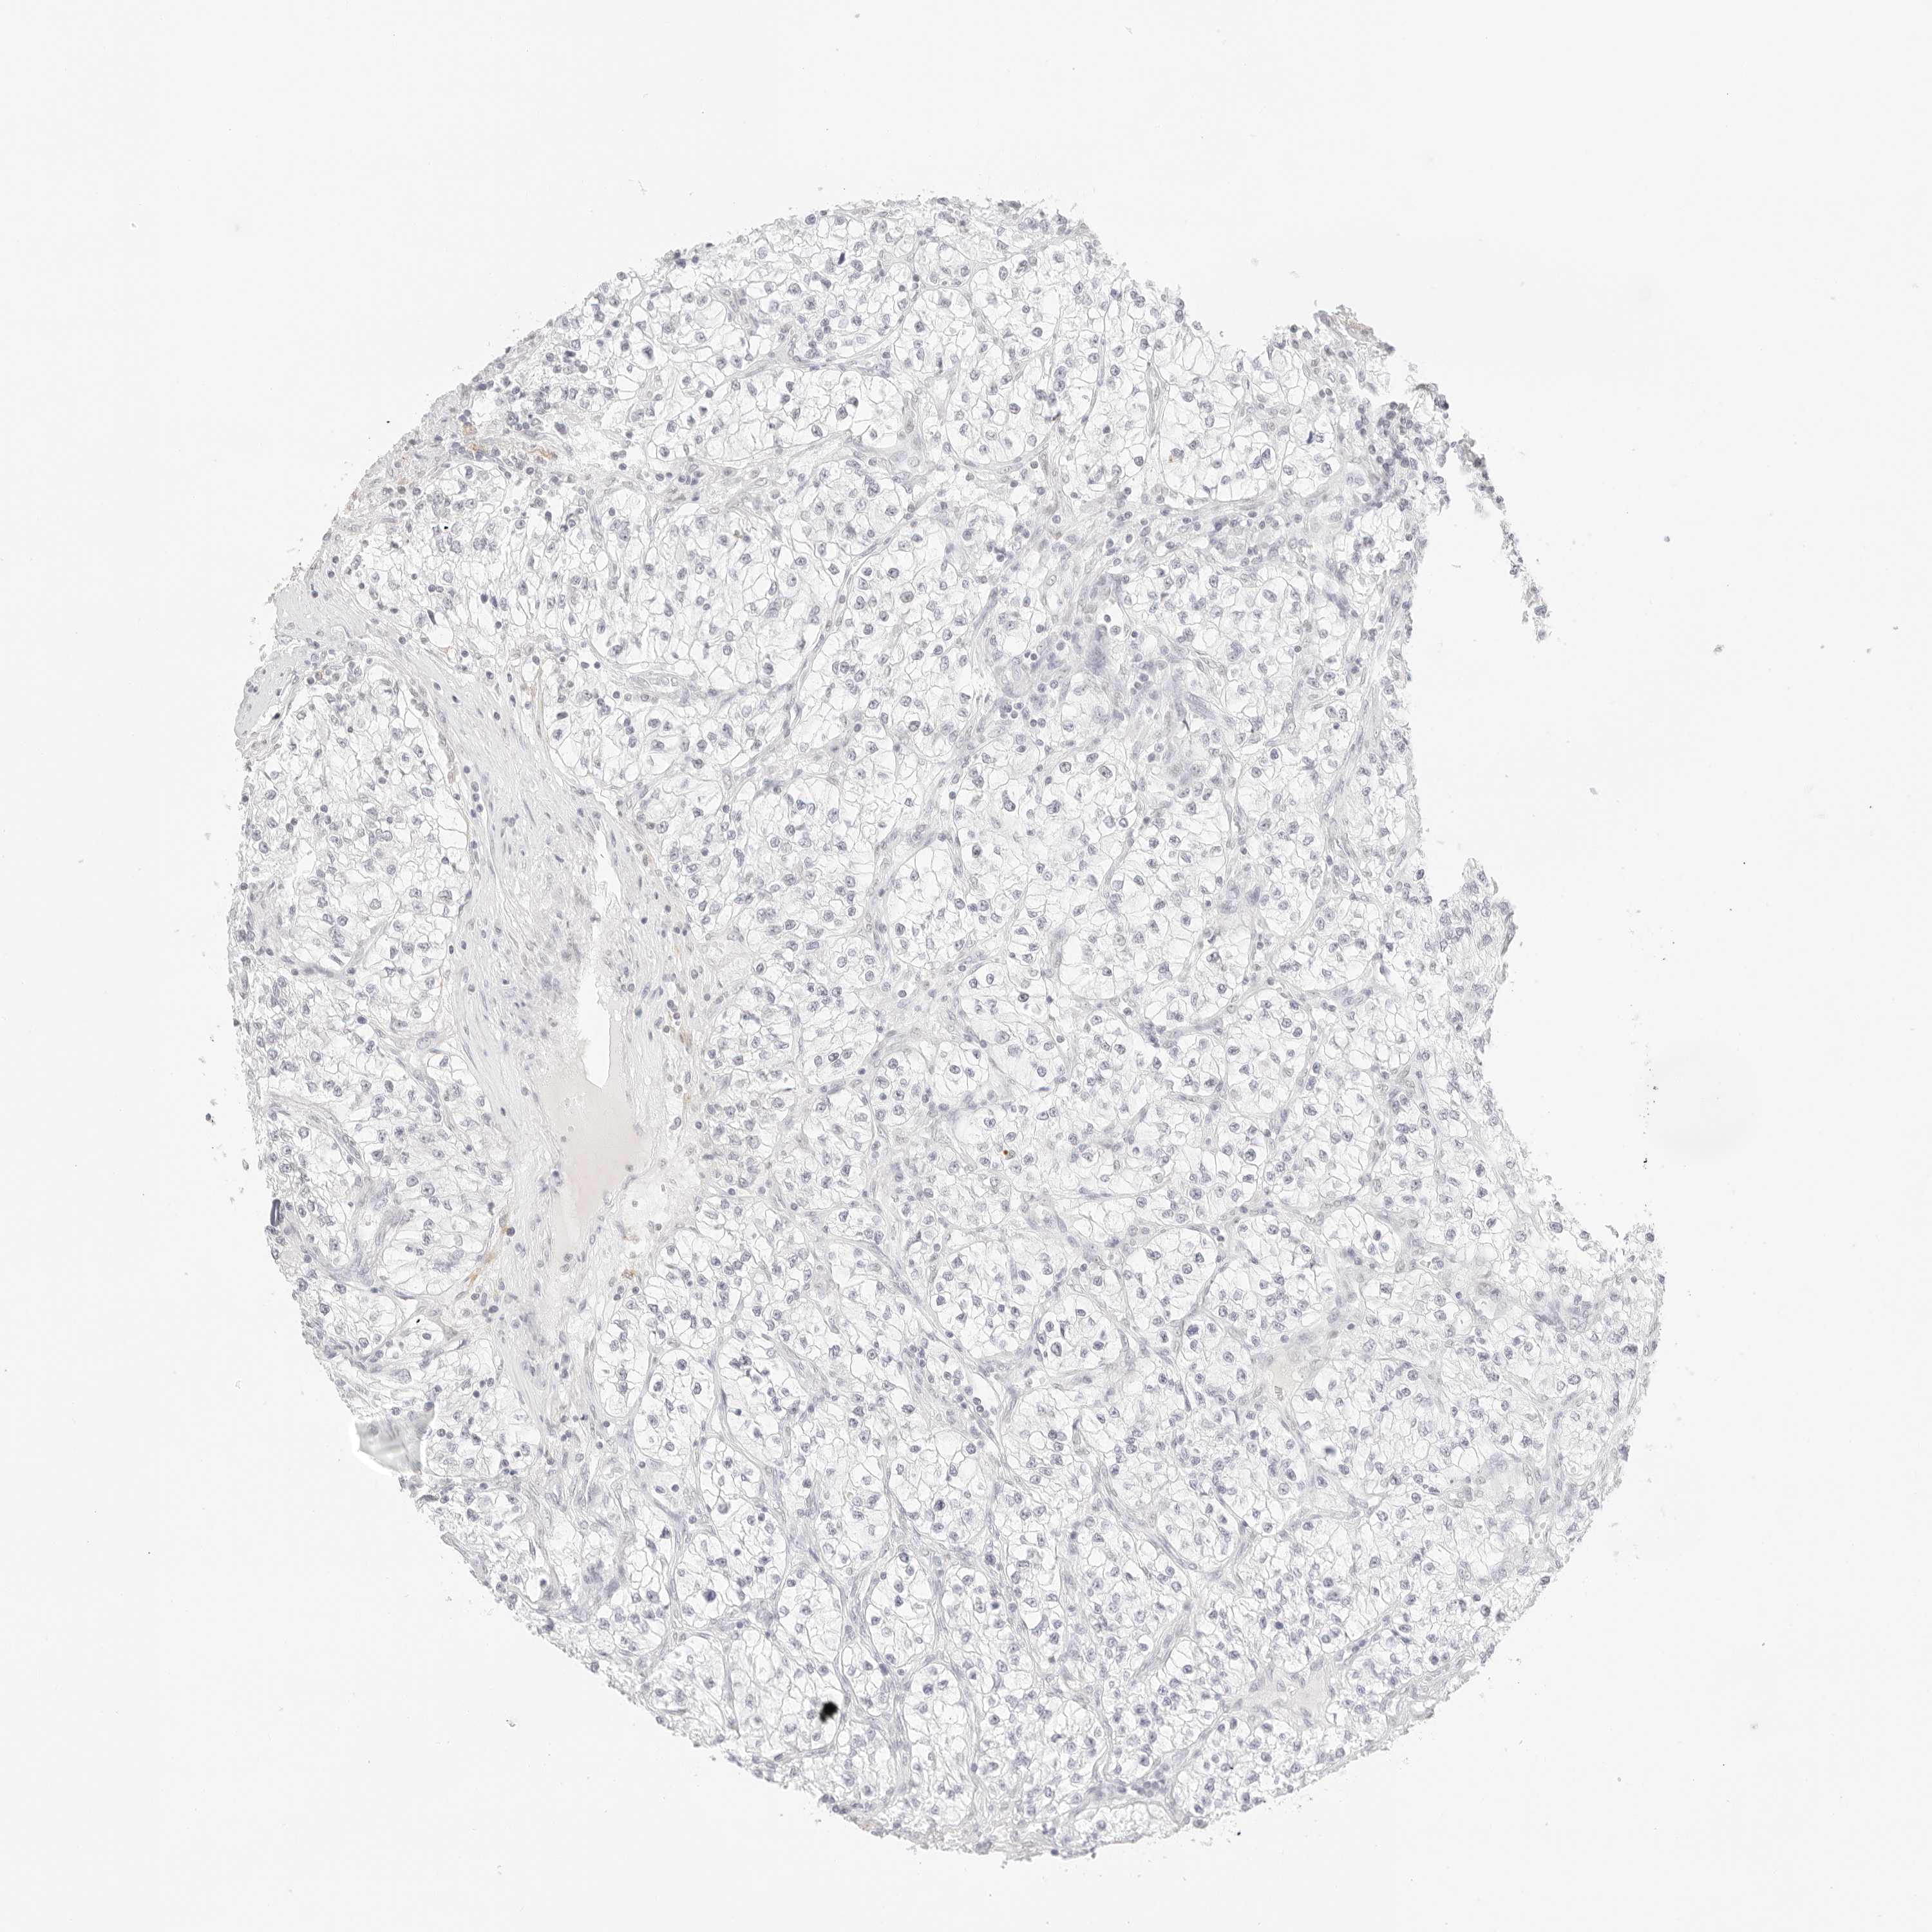

KIDNEY RENAL CLEAR CELL CARCINOMA (TCGA) - Interactive survival scatter ploti

The Survival Scatter plot shows the clinical status (i.e. dead or alive) for all individuals in the patient cohort, based on the same data that underlies the corresponding Kaplan-Meier plots. Patients that are alive at last time for follow-up are shown in blue and patients who have died during the study are shown in red.

The x-axis shows the expression levels (FPKM) of the investigated gene in the tumor tissue at the time of diagnosis. The y-axis shows the follow-up time after diagnosis (years). Both axes are complimented with kernel density curves demonstrating the data density over the axes. The top density plot shows the expression levels (FPKM) distribution among dead (red) and alive patients (blue). The right density plot shows the data density of the survived years of dead patients with high and low expression levels respectively, stratified using the cutoff indicated by the vertical dashed line through the Survival Scatter plot. This cutoff is automatically defined based on the FPKM cutoff that minimizes the p-score. The cutoff can be changed by dragging the vertical line or by entering a cutoff value in the square labeled "Current cut-off".

Under the Survival Scatter plot the p-score landscape (black curve; left axis) is shown together with dead median separation (red curve; right axis). Dead median separation is the difference in median mRNA expression between patients who have died with high and low expression, respectively. It is calculated as follows: median FPKM expression of dead patients with high expression - median FPKM expression of dead patients with low expression. This is intended to aid the user in visually exploring custom cutoffs and the associated p-scores and dead median separation.

Individual patient data is displayed and can be filtered by clicking on one or more of the category buttons on the top of the page. Categories describing expression level and patient information include: high, low, alive, dead, female, male and tumor stages. The scale of the x-axis can be toggled between linear and log-scale by clicking on the "x log" button. Mouse-over function shows TCGA ID, patient information and mRNA expression (FPKM) for each patient.

& Survival analysisi

Kaplan-Meier plots summarize results from analysis of correlation between mRNA expression level and patient survival. Patients were divided based on level of expression into one of the two groups "low" (under cut off) or "high" (over cut off). X-axis shows time for survival (years) and y-axis shows the probability of survival, where 1.0 corresponds to 100 percent.

FBLN5 is not prognostic in Kidney Renal Clear Cell Carcinoma (TCGA)

Best expression cut offi

Based on the FPKM value of each gene, patients were classified into two groups and association between prognosis (survival) and gene expression (FPKM) was examined. The best expression cut-off refers the FPKM value that yields maximal difference with regard to survival between the two groups at the lowest log-rank P-value. Best expression cut-off was selected based on survival analysis .

When clicking on this number, the vertical dashed line indicating cut-off, the interactive survival plot, and the Kaplan-Meier curve will be adjusted to show results based on the best expression cut-off.

: 13.49

Average pTPM 35.0

Number of samples 521